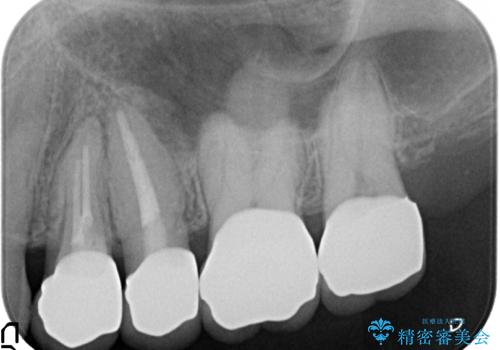

- 左上の奥歯を綺麗にしたいといらっしゃった方の症例です。

左上4、5、6、7番目の歯をオールセラミッククラウンにより補綴しました。

今回用いたオールセラミッククラウンは、ジルコニアフレームという白い素材の上にセラミックを盛っているため審美性が非常に高いのが特徴です。

またジルコニアは人工ダイヤモンドの材料にも使われているほど高い強度を持っており、そのためオールセラミッククラウンは審美性だけでなく、奥歯やブリッジの補綴も可能とするクラウンです。